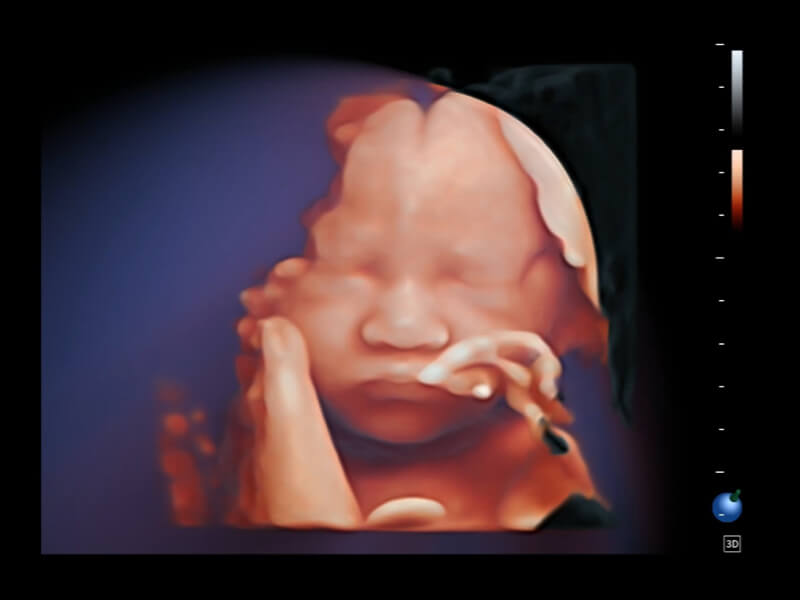

Diese neuen Perspektiven ermöglichen die Betrachtung der Anatomie aus Volumenperspektiven, mit fortschrittlicher Bewertung und intelligenten Scan-Tools. Sie bieten Klinikern mehr Informationen und helfen, Anomalien früher als je zuvor zu identifizieren.

S-Live Studio S-Fetus AVC Follicle HyCoSy mit SPI S-PF (3D) S-ERA

• S-Live Studio liefert eine brillante, realistische Hautvisualisierung in Echtzeit, indem es die Lichtausbreitung auf der Hautoberfläche simuliert und so die Tiefe und Authentizität des dreidimensionalen Bildes bereichert.